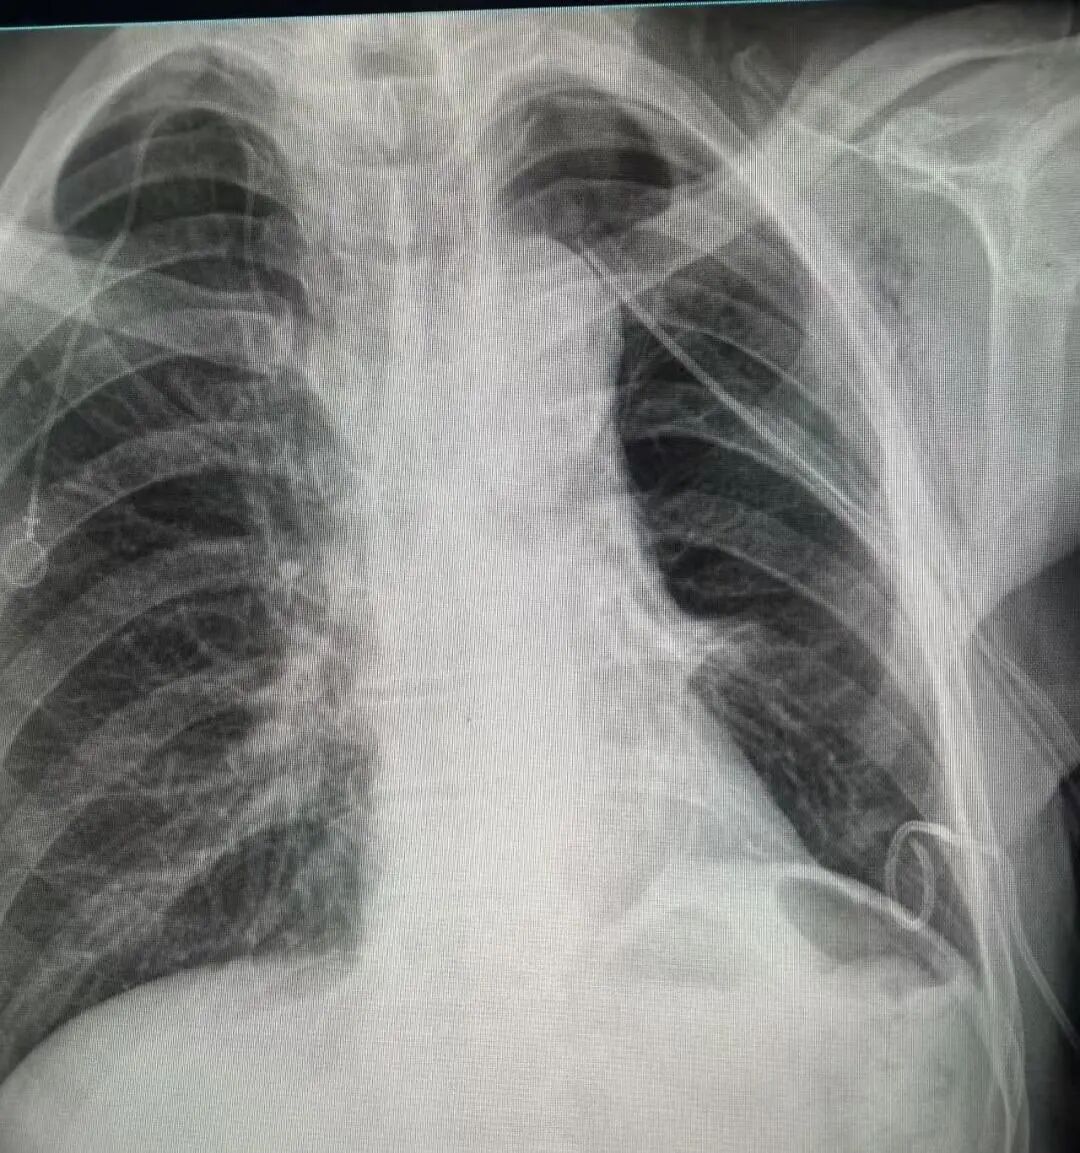

术后胸片

术后病理:切除组织未见残留癌细胞,达到根治效果